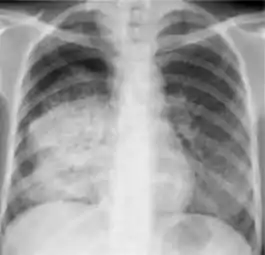

Radiology (X-rays) is used in the diagnosis of tuberculosis. Abnormalities on chest radiographs may be suggestive of, but are never diagnostic of TB, but can be used to rule out pulmonary TB.

Tuberculosis creates cavities visible in x-rays like this one in the patient's right upper lobe.

A posterior-anterior (PA) chest X-ray is the standard view used; other views (lateral or lordotic) or CT scans may be necessary.

In active pulmonary TB, infiltrates or consolidations and/or cavities are often seen in the upper lungs with or without mediastinal or hilar lymphadenopathy.[1] However, lesions may appear anywhere in the lungs. In HIV and other immunosuppressed persons, any abnormality may indicate TB or the chest X-ray may even appear entirely normal.[1]